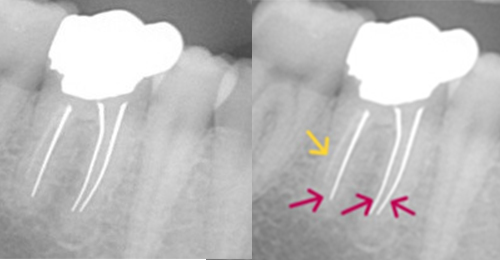

薬が真ん中までしか入っていないため、膿が貯まっている。

ファイルが折れて骨に刺さっている。

奥の歯も薬が入っていない。

実際は2根管だった。

薬が根尖までしっかりはいっていない。

化膿している

小豆大の病巣

ワッテが入っていた 病巣も大きい

突き出たガッタパーチャポイントと大きな病巣

なぜか根管途中から突き出たガッタパーチャポイント